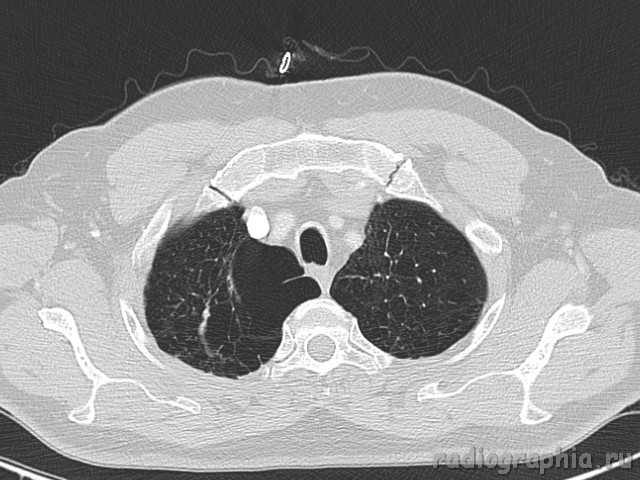

Одиночный узел правого лёгкого.

На рутинном снимке ОГК, был выявлен одиночный узел; по протоколу выполнили КТ. Какое было бы ваше заключение; и как бы Вы поступили если у вас нет возможности выполнять КТ?